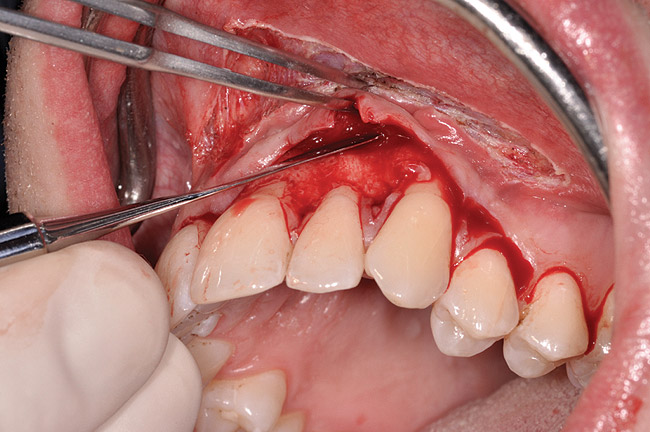

Fig 3. Example of laser-assisted split-thickness

vestibuloplasty.

Figure 3

The authors have introduced a laser-assisted vestibuloplasty approach (LAVA) procedure that is designed to prevent recurrent recession after surgical correction, which has been reported in the literature.29,38 This first involves a flap procedure for insertion of the dermal matrix graft material to be used to achieve root coverage and increase zones of existing attached keratinized tissues. To complete the vestibuloplasty procedure, the surgeon separates the mucosal tissues apical to the preexisting mucogingival junction in the area of the teeth exhibiting gingival recession. The authors advocate using a Nd:Yag laser with a power setting at 5 watts to accomplish the vestibuloplasty and release any excessive muscle attachments or frenal pulls in the affected areas (Figure 3).

The flap approach follows an incision design where the crest of the papilla is preserved and a V-type incision is made in the papillary tissues (Figure 4). This allows the preexisting papillary tissues in the area just inferior to the contact point of the natural teeth affected to be used as a tissue bed to provide vascularization to the flap/dermis complex. Prior to securing the dermal matrix tissue, the papillary tissues that remain after the incision technique outlined must be de-keratinized by using a #4 round diamond bur. This allows for the introduction of initial blood flow and vascularization of the dermal matrix tissues and nourishment of the coronally repositioned flap in the critical area of the interproximal papillary tissues. After securing the dermal matrix tissue from the palatal/lingual aspect of the teeth being treated and coronally repositioning the buccal flap, closure is achieved using an interrupted sling suturing technique.